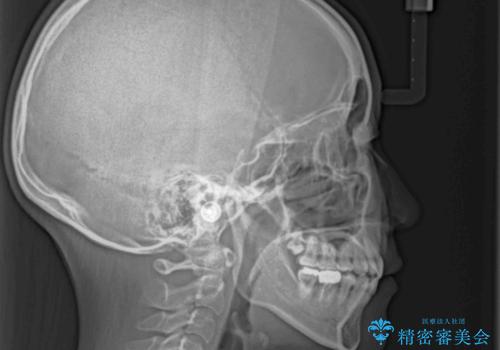

- 口元の突出感を気にして来院された患者様です。

上下左右の第一小臼歯4本を抜歯して口元を下げる治療計画としました。

裏側矯正特有の抜歯スペースに前後の歯が倒れ込む状態が長く続き、改善に長期間を要しました。